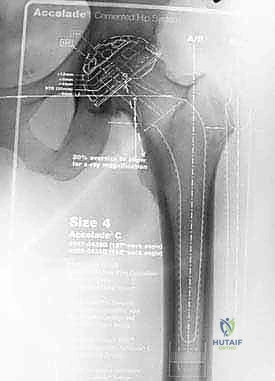

تثبيت كسور عظم العضد القريب بالمسامير النخاعية: دليل شامل للمرضى مع الأستاذ الدكتور محمد هطيف

تعرف على تثبيت كسور عظم العضد القريب بالمسامير النخاعية، الأسباب، الأعراض، العلاج، والتعافي. الأستاذ الدكتور محمد هطيف خبير جراحة العظام في…